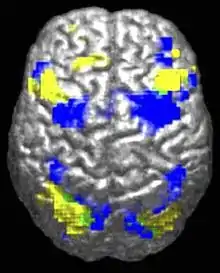

Differences in activity between autistic (yellow) and non-autistic brains.